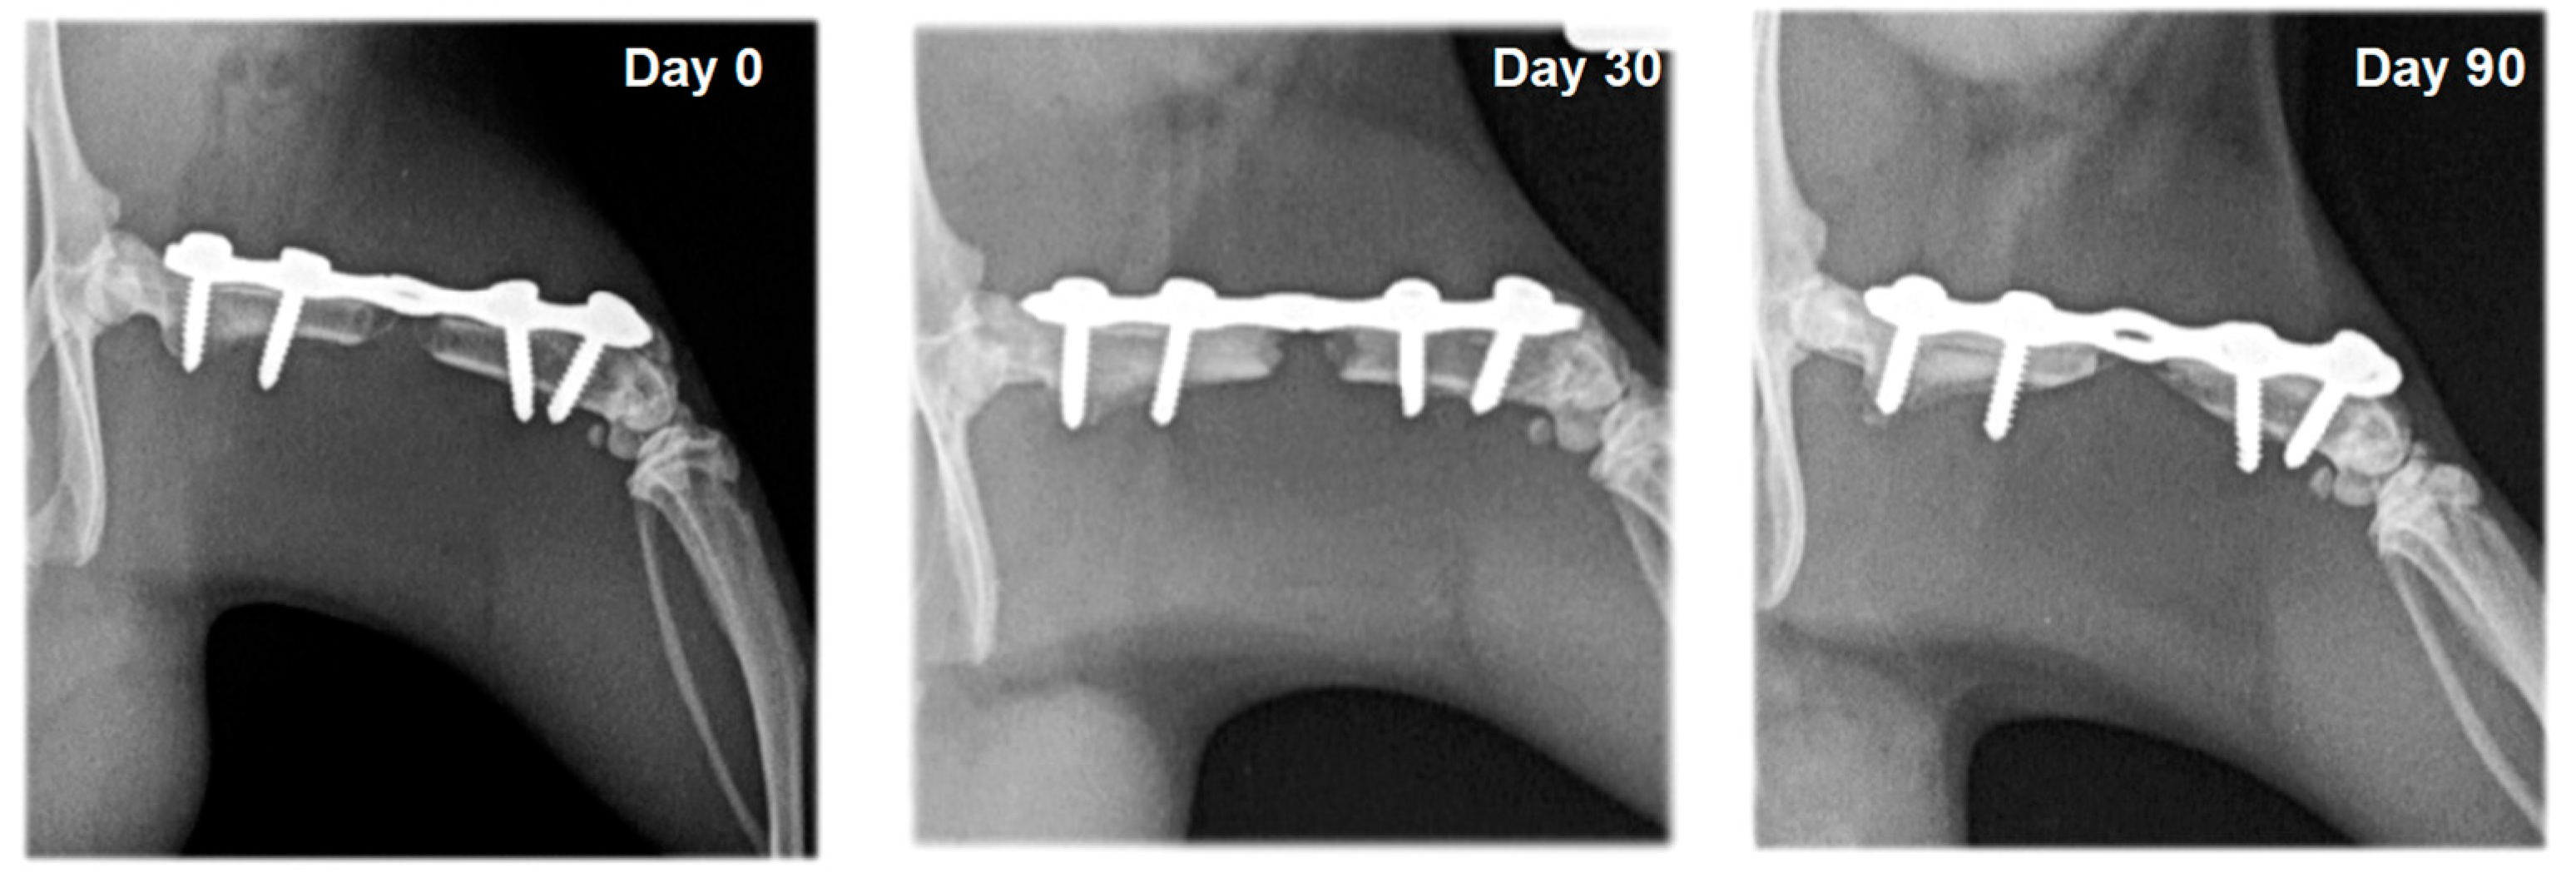

On radiographs, newly formed bone appears as a non-homogenous increased radiopacity (Figure 5 and Figure 6).

Figure 5.

Serial craniocaudal radiographs of rat femurs from experimental group F3 on post-operative days 0, 30 and 90.

Figure 6.

Serial craniocaudal radiographs of rat femurs from experimental group F4 on post-operative days 0, 30 and 90.

In rats whose defects were filled with bone substitute, the xenograft was visualized with strong heterogeneous radiopacity and was radiologically visible until the end of the experiments. Bone integration between the xenograft and the host bone was not observed in rats from group F5, which were treated with bone substitute and saline. Bone formation was evident in animals from group F6, whose defects were filled with bone substitute and erythropoietin (Figure 7 and Figure 8). A statistically significant difference (p < 0.05) between the healing scores of these two groups was observed on the 30th post-operative day (Table 1).